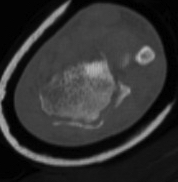

CT

Radial styloid + dorsal rim fractures